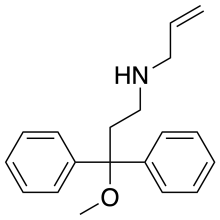

Others

- 3-(3-Methoxyphenyl)-3-ethoxycarbonyltropane

- AD-1211

- AH-7921

- Axomadol

- Azaprocin

- BDPC

- Bisnortilidine

- BRL-52537

- Bromadol

- Bromadoline

- Ciprefadol

- Ciramadol

- Doxpicomine

- Enadoline

- Faxeladol

- GR-89696

- Herkinorin

- ICI-199,441

- ICI-204,448

- Ketamine

- KNT-42

- LPK-26

- Lufuradom

- Metofoline

- MT-45

- Desmethylclozapine

- Nexeridine

- NNC 63-0532

- Nortilidine

- O-Desmethyltramadol

- Phenadone

- Phencyclidine

- Prodilidine

- Profadol

- Ro64-6198

- Salvinorin A

- Salvinorin B ethoxymethyl ether

- Salvinorin B methoxymethyl ether

- SB-612,111

- SC-17599

- RWJ-394,674

- TAN-67

- Tapentadol

- Thiobromadol (C-8813)

- Tifluadom

- Tilidine

- Tramadol

- Trimebutine

- U-47700

- U-50,488

- U-69,593

- Viminol

- 1-(4-Nitrophenylethyl)piperidylidene-2-(4-chlorophenyl)sulfonamide (W-18)